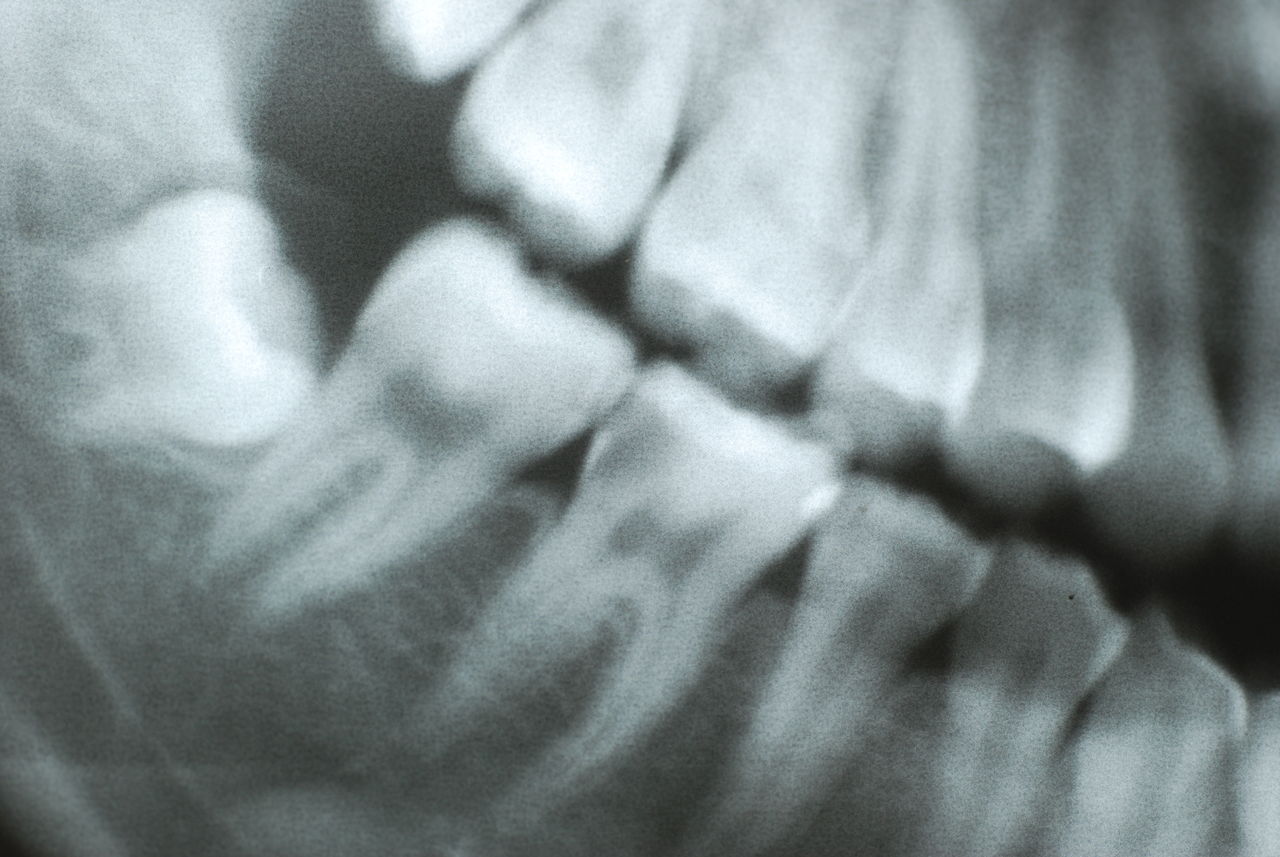

レントゲンでは小さいですが、こう言う虫歯が一番怖いのです。

隣の14歳大臼歯がひどい虫歯になり治療不可能になりつつある状態のレントゲン